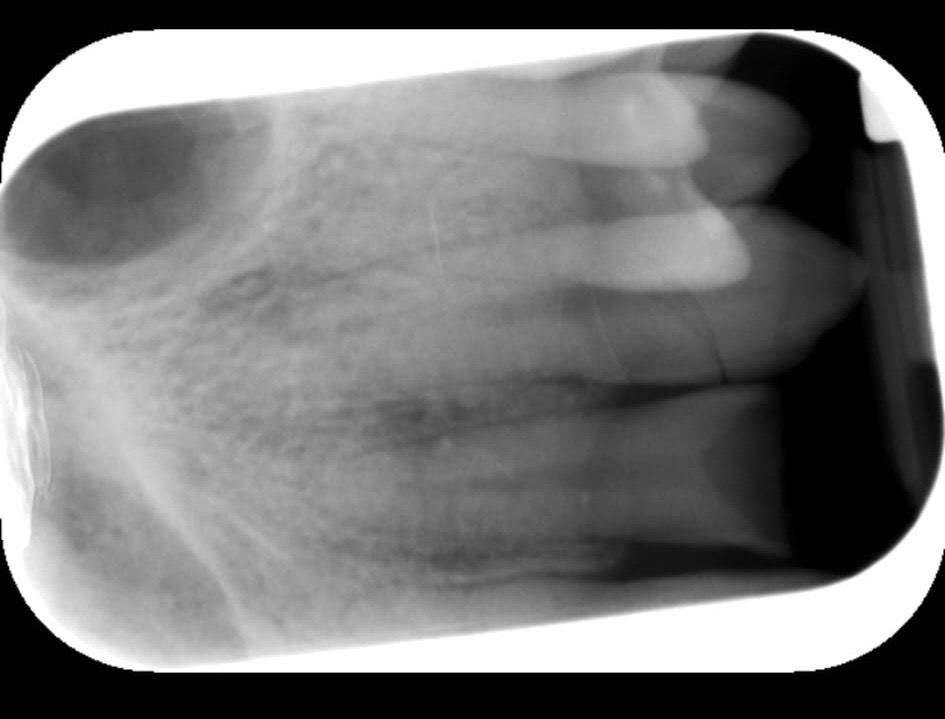

Kaiden suffered a bruised cheekbone, a black eye, concussion and extensive trauma to his teeth.

Altogether, he has six broken teeth.

5 root canals

Specialist surgery, as one tooth has shattered in several places inside the jaw and cannot be removed without a surgical procedure

In the last 24 hours, Kaiden has seen three different dentists. All of them have said this is an extremely severe case of trauma. One dentist, with 20 years of experience, said she had never seen injuries like this from football—only from major accidents.